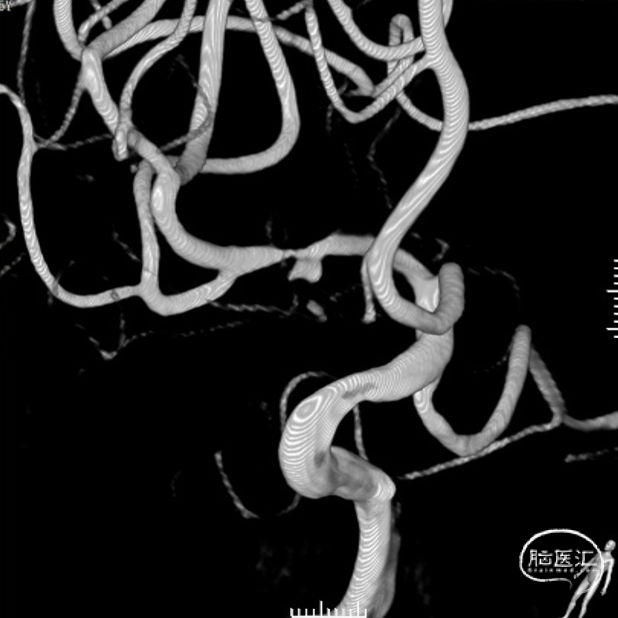

颅颈部CTA:右侧大脑中动脉局限性瘤样扩张伴其近远端管腔狭窄。

脑血管造影:右侧大脑中动脉M1段局部瘤样突起,远端重度狭窄,考虑右侧大脑中动脉M1段夹层动脉瘤。

右侧颈内动脉正侧位和右侧大脑中动脉工作位造影。

治疗之前3D和工作位(测量病变处近远端血管管径,M1近端1.9mm,M1远端1.7mm)。